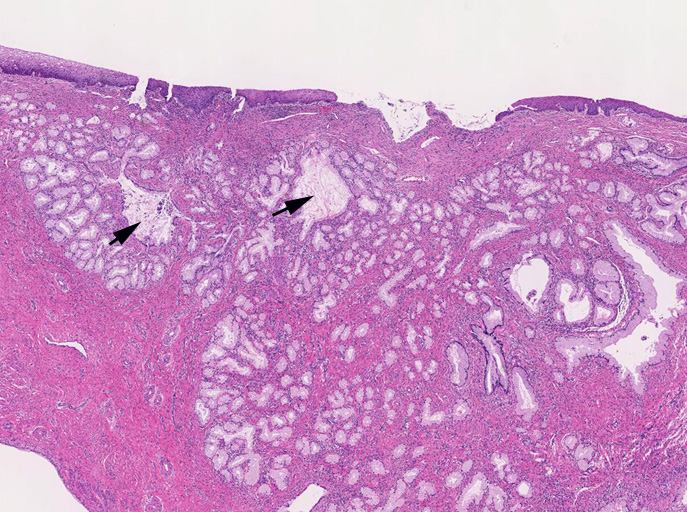

子宮頚管腺に類似した高円柱上皮よりなる腺管の著明な増生を認める。これらは大型で拡張した導管様腺管と,それを囲繞するように配列する分葉状構造をしめす小型腺管からなり, 嚢胞状に拡張した腺管も随所に認められる。最深部にみられる腺上皮は, 嚢胞状に拡張した腺管の一部と考えられる。

しかしながら完全に異型がないとはいえず分葉構造を保持しているものの上皮の内腔への乳頭状増殖や重層化, 軽度から中等度の核腫大, クロマチン増加, 核分裂像をしめす腺が認められる---> with atypia

LEGHは大型導管に類似した拡張腺管の周囲に中型から小型の腺管が分葉状に増生するのが特徴。小型腺管を構成する高円柱上皮細胞質は正常頸管腺上皮の細胞質が淡明あるいは, やや青白い色調を呈するのに対し淡明ないし淡好酸性となる傾向にある。

loupe像では, 拡張した導管を中心に高円柱上皮からなる腺管が分葉状に配置する所見が認められる。